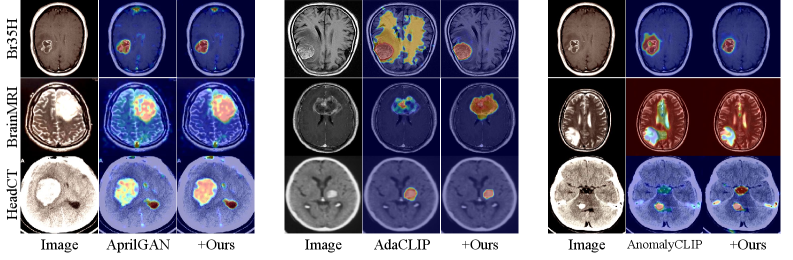

IV-C4 Qualitative Comparison

Fig. 5 shows qualitative results across medical (left) and industrial (right) datasets. Text-guided baselines (AprilGAN, AdaCLIP, AnomalyCLIP) frequently over-activate irrelevant regions (e.g., spurious highlights in MPDD and ISIC) or miss subtle defects (e.g., boundary losses in Kvasir and DAGM). With our method, anomaly maps become cleaner and more discriminative: medical lesions exhibit sharper contours, and industrial defects (scratches, texture inconsistencies) are localized without redundant noise. The results demonstrate that refining and denoising cross-modal matching cost enhances anomaly–text correspondence and leads to more reliable localization across heterogeneous datasets.